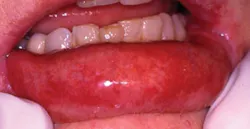

GVHD has developed in Mrs. Jones, and she has very evident oral lesions, as well as extensive lesions on her lips. The skin is affected with pigmentation in various areas on her extremities.

The general physician has noted in his comments that eating has been difficult for the patient, and her oral lesions need improvement. The patient reports dryness, difficulty in opening her mouth (the similar scarring that is found in scleroderma is related to restricted oral tissue opening), and the pain is very intense at times. Because of these factors, Mrs. Jones has been consuming liquids with some soft foods (see Figure1).